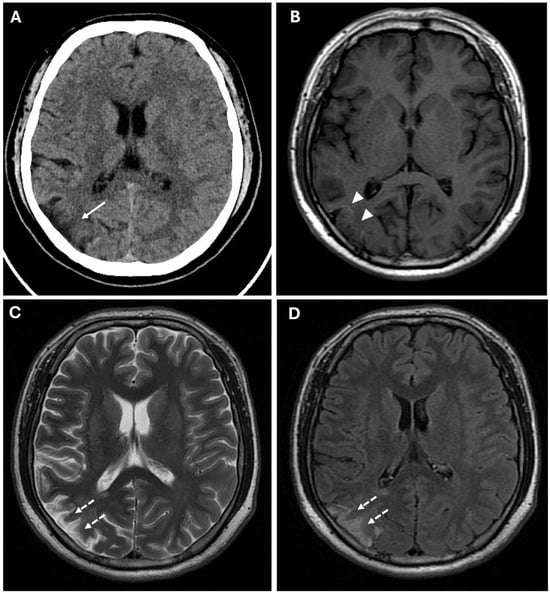

These findings suggested acute ischemic lesions in the right middle cerebral artery territory. There were no hemorrhagic lesions or mass effect on the encephalic parenchyma. Computed tomography angiography (CTA) examination showed reduced caliber and parietal irregularity of M1–M2 tracts of the middle cerebral artery bilaterally, with steno-occlusive tract-like changes. Additionally, vascular ectasia of deep lenticular arteries and the right anterior cerebral artery were also detected (Figure 2).

Figure 2. (A,B) CTA images in axial (A) and coronal (B) views, using a Maximum Intensity Projection (MIP) reconstruction, show reduced caliber and parietal irregularity of the M1-M2 tract bilaterally (white arrows) with severe stenotic tract in the left MCA (white arrowheads). (C) 3d MRA sequence shows multiple steno-occlusive changes in M1-M2 bilaterally (white arrows), irregular caliber of the right ACA (white dotted arrows), and right PCA (yellow dotted arrows). (D) Volume rendering reconstruction of CTA shows abnormal collateral perforators (white arrowheads).

MRA confirmed the reduced caliber and wall irregularities with steno-occlusive changes in M1–M2 tracts of the middle cerebral artery bilaterally, predominantly on the right. The A2 segment of the right anterior cerebral artery (ACA) and the P2 segment of the right posterior cerebral artery (PCA) also showed irregular caliber due to alternations of stenotic and dilated tracts (Figure 2).